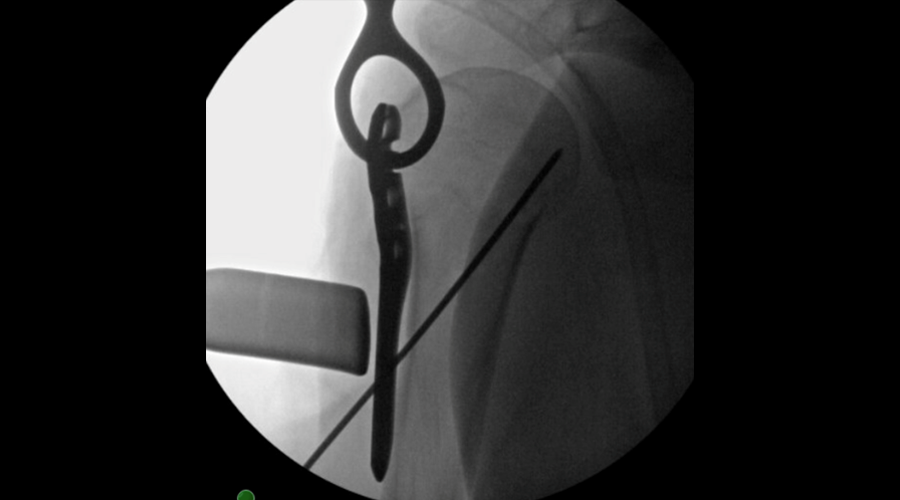

The patient was treated with open reduction and internal fixation (ORIF). First, the fracture was reduced (Fig 2a-b). There was an attempt at closed reduction with continued displacement. Then an open reduction through a deltopectoral approach was performed. After direct reduction, a 1.6 mm K wire was placed along the anterolateral humeral surface. The provisional plate placement and reduction are depicted in Fig 3.